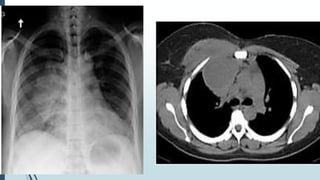

25 yrs. Male with fever & chest pain for few

days

25 yrs. Malewith fever & chest pain for few days